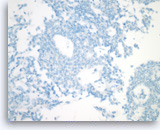

Pancreatic endocrine neoplasm #1,

Pancreas FNA, Cell Block.

The tumor cells are present singly or in sheets and groups without a crisp, normal acinar arrangement.

40X

Pancreatic endocrine neoplasm #1,

Pancreas FNA, Cell Block.

The tumor cells are present singly or in sheets and groups without a crisp, normal acinar arrangement.

40X